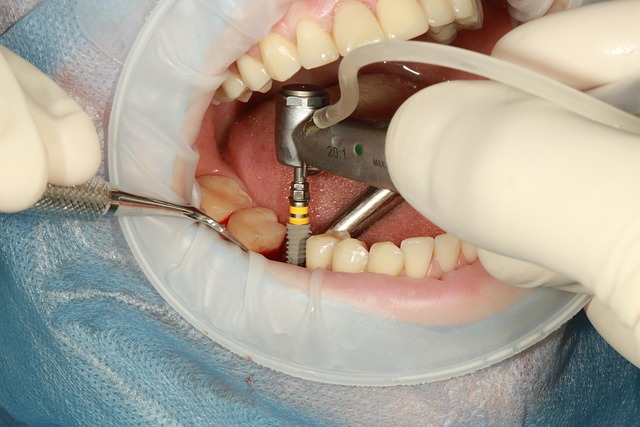

Cerrahi Aşama

Lokal anestezi uygulandıktan sonra diş dikkatlice çekilir. Çekim bölgesi özenle temizlenir ve enfeksiyon varsa uzaklaştırılır. Kemik dokusuna özel frezlerle yuva açılır ve implant uygun pozisyonda yerleştirilir. İmplant üzerine geçici bir protez adapte edilir.